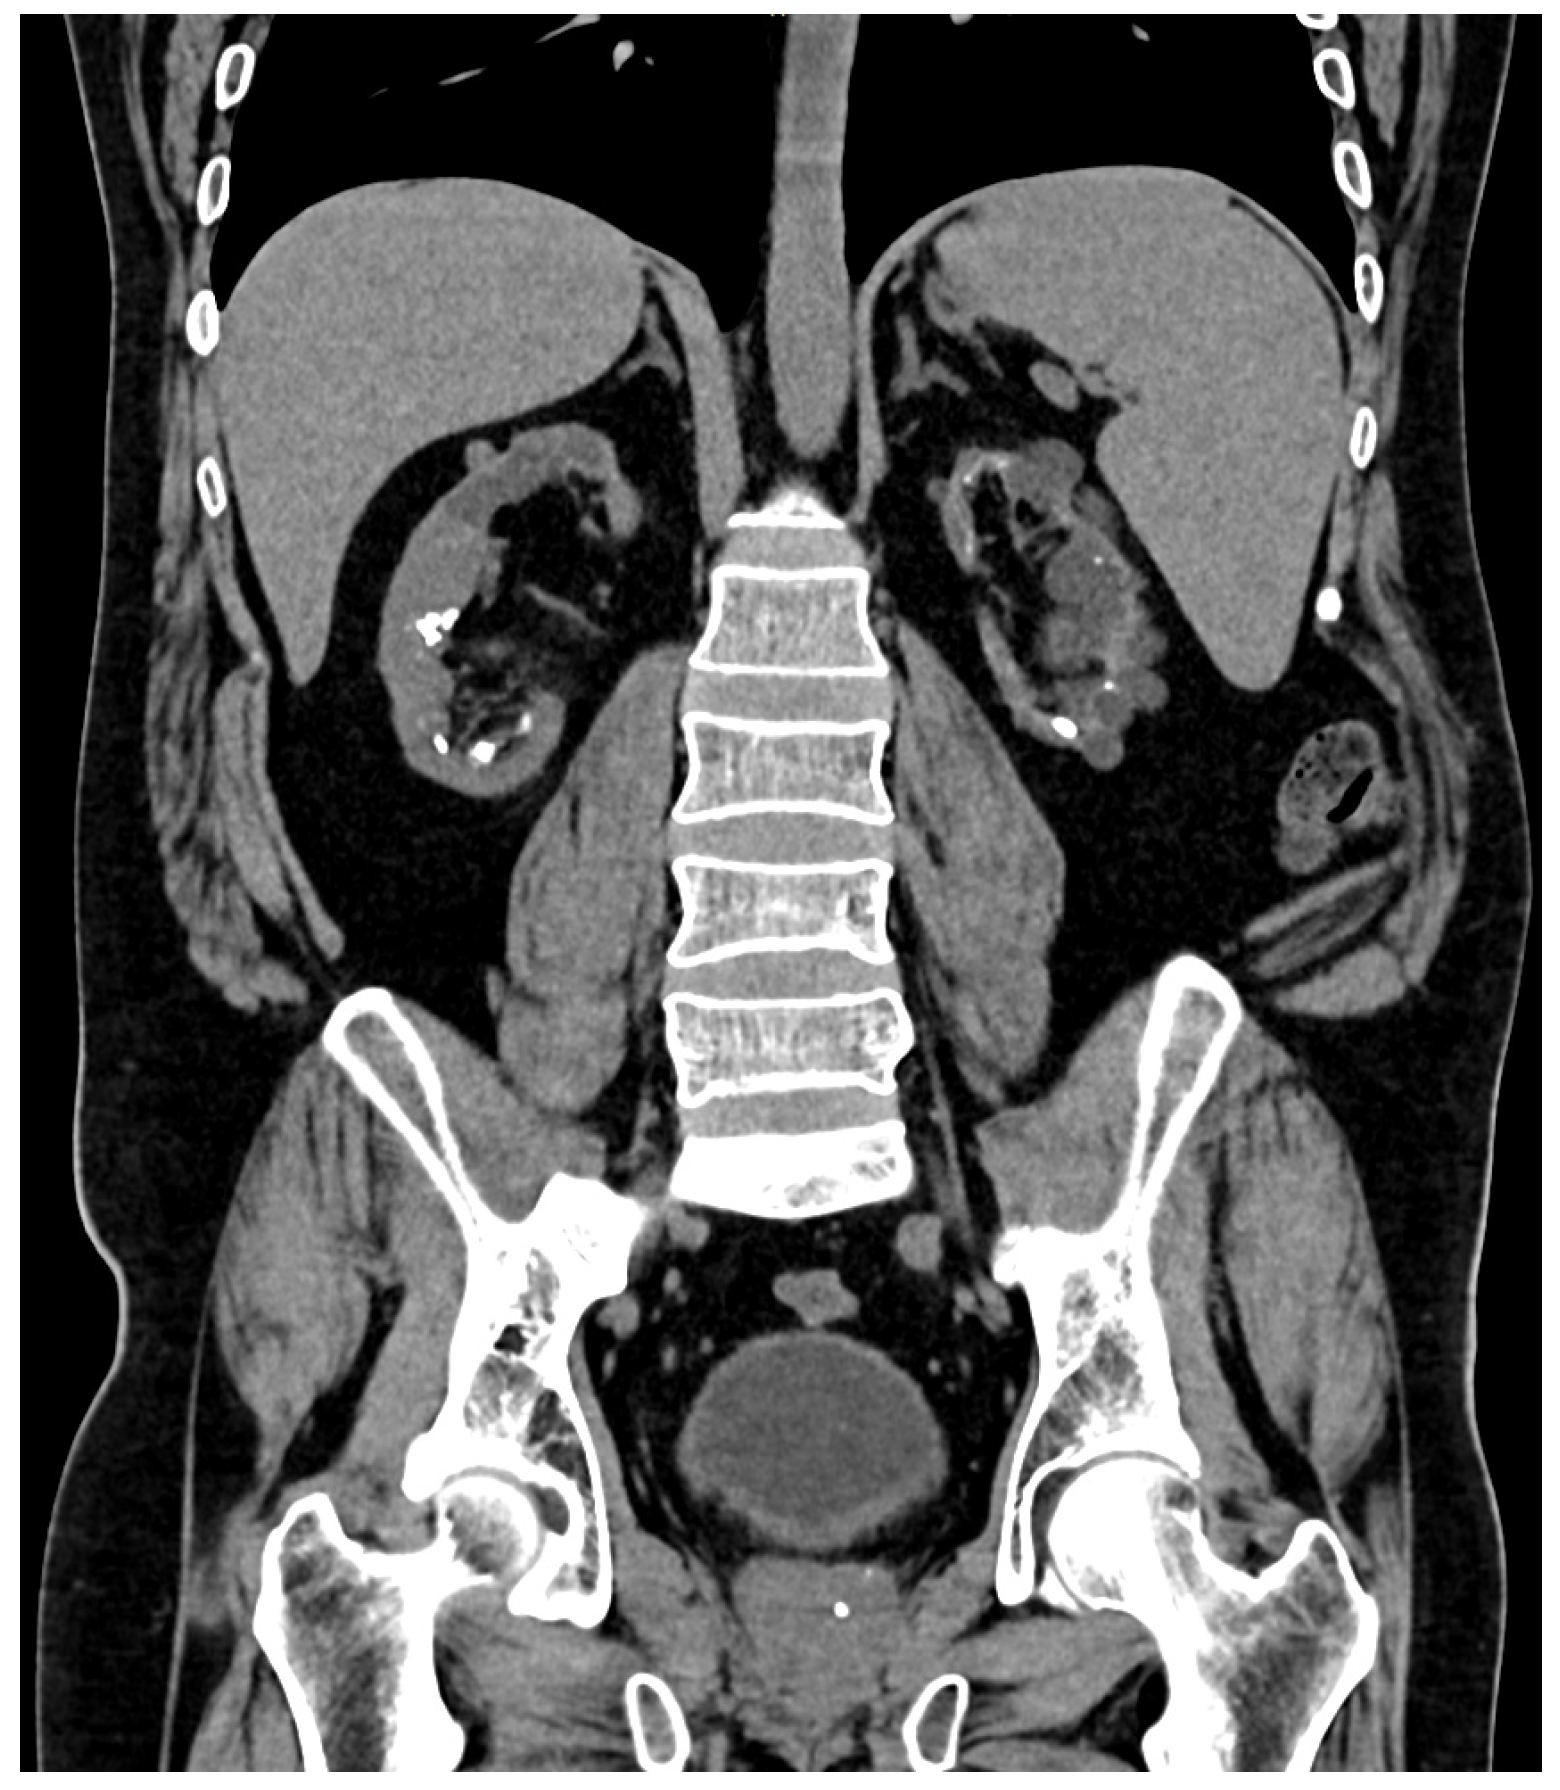

The prevalence of urinary lithiasis is progressively increasing, and it is estimated that approximately 5–10% of the general population will present lithiasis at some point in their lives [18]. According to the series studied, up to 11% of kidney stones in adult patients and up to 30% in children have a monogenic origin [8,19]. In DD, concomitant hypercalciuria and kidney stones appear to be more frequent in CLCN5 mutations [12], and hypophosphatemia and hyperphosphaturia are considered independent risk factors for the development of kidney stones and nephrocalcinosis [20]. In our patients, the kidney stones are predominantly composed of calcium phosphate. Four of the six patients developed kidney stones despite undergoing various procedures such as URS, RIRS, ureterolithotomy, ESWL, or ECIRS (Figure 1 and Figure 2), while two remained free of kidney stones at their last radiological follow-up (cases 3 and 5). One patient (case 3) has not had kidney stones during the course of the disease; however, he suffers severe nephrocalcinosis (Figure 3), which has led to end-stage CKD.

Figure 1.

Bilateral lithiasis and microlithiasis in atrophic kidneys in case number 1.